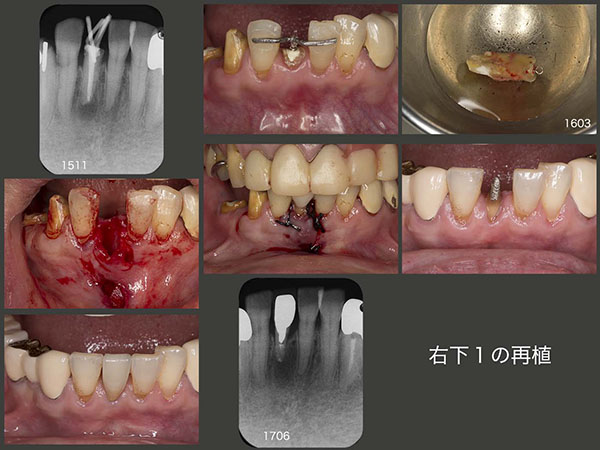

ここで右下1について述べる.まず通常の感染根管処置を施したが,治癒せず,フィステルが再出現した.歯根端切除術を行うか迷ったが,今回はここも挺出力をかけ,歯の動揺が生じたうえで再植した.根尖付近に人工的穿孔が認められ,スーパーボンドにて封鎖した.1年3ヵ月経過をみたうえで,メタルボンド冠を装着した.患者さんには,ここでは硬食品を咬まないでくださいとお願いしている.